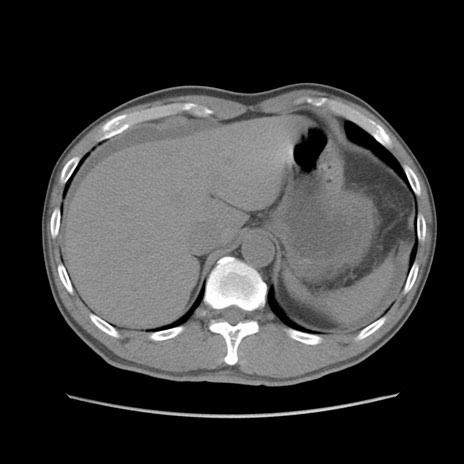

症例56 CT(横断像)

脂肪ウインドウ